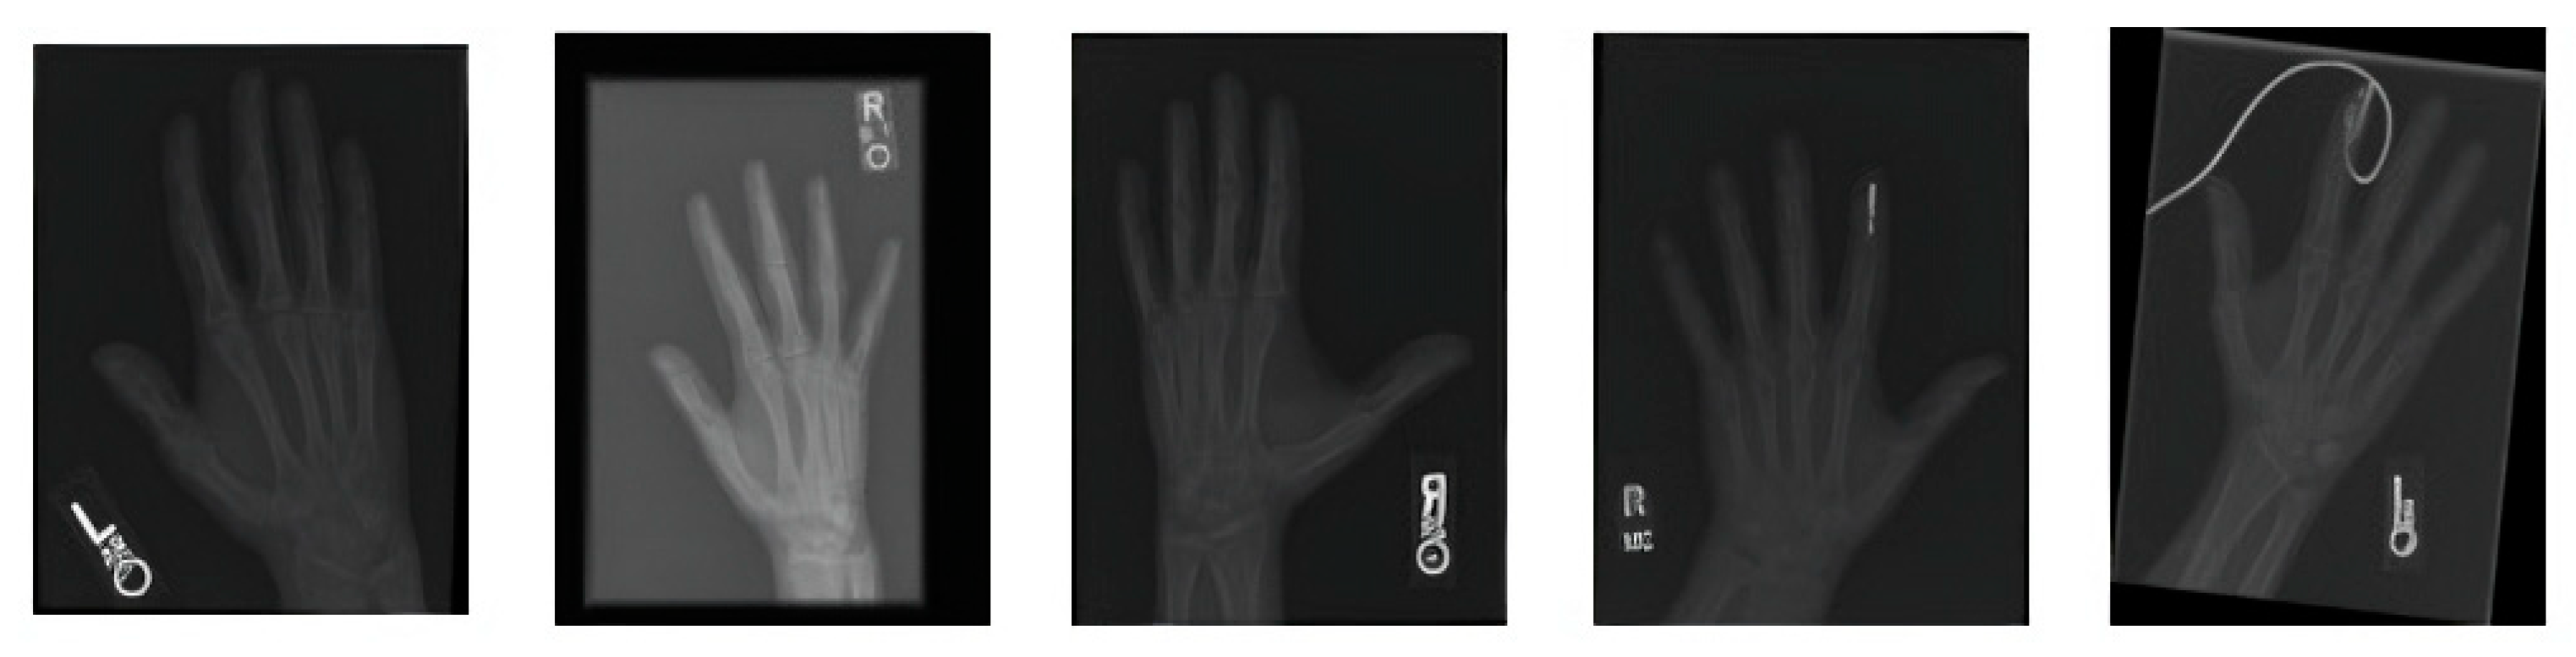

Figure 2 covers the visualization of the mini set of images after transforming it via data augmentation. Image transformations including rotation, scaling, flipping, and brightness modifications have been added to these images to make the training dataset more lively and informative. The artificial images with variety boosted the machine learning models and led to better robustness and generalization ability of these models in case the real-world data varied a lot.

Figure 2. A sample of images after data augmentation.